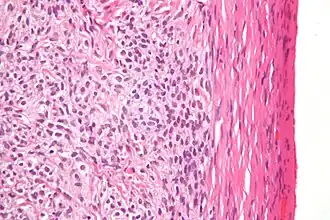

Fort grossissement d'un thécome, coloration à l'hématoxyline et à l'éosine.

Caractéristiques pathologiques

Grossièrement, la tumeur est solide et jaune.

Grossièrement et au microscope, il se compose du cortex ovarien.

Au microscope, les cellules tumorales ont un cytoplasme abondant rempli de lipides.